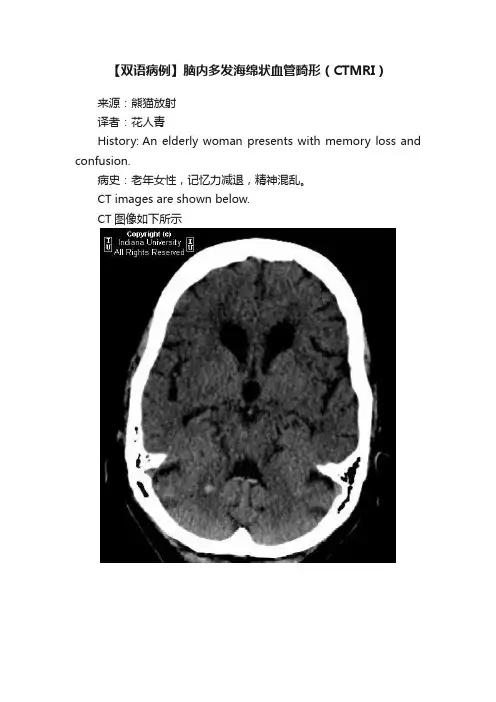

【双语病例】脑内多发海绵状血管畸形(CTMRI)来源:熊猫放射译者:花人青History: An elderly woman presents with memory loss and confusion.病史:老年女性,记忆力减退,精神混乱。

CT images are shown below.CT图像如下所示MR imagesHere are some panels of fluid-attenuated inversion-recovery (FLAIR) and gradient-recalled echo (GRE) images.水抑制图像及GRE序列图像如下所示。

FindingsCT: CT shows a 5-mm focus of hyperattenuation with surrounding hypoattenuation within the superior right cerebellar hemisphere. Diffuse sulcal and ventricular prominence, compatible with diffuse cerebral volume loss. Scattered geographic regions of relative hypoattenuation within the bilateral periventricular white matter, compatible with small-vessel ischemic disease.MRI: MRI shows numerous small, rounded areas of signal dropout, best appreciated on axial GRE, within the cerebellum, right paracentral pons, left posterior and ventral thalamus, and corona radiata.影像表现:CT:右小脑半球偏上部可见一直径约5mm高密度灶,周围环绕低密度影。